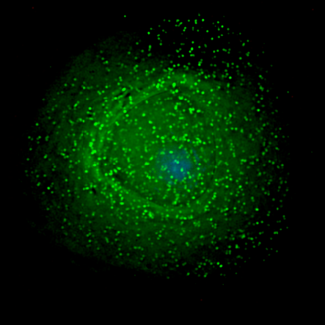

VIH. (Foto: Gross L, PLoS Biology Vol. 4/12/2006, e445. doi:10.1371/journal.pbio.0040445)